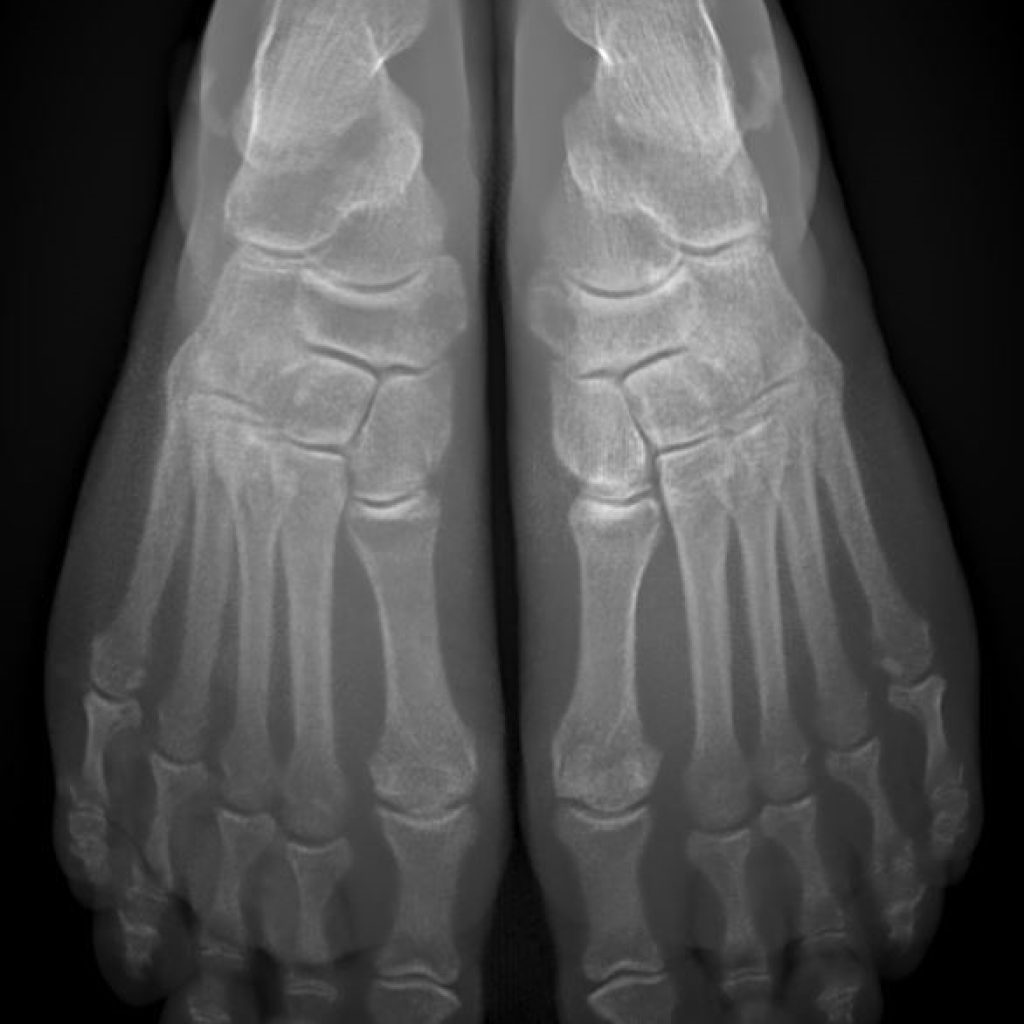

Il s’agit d’un appareil type cone beam permettant d’étudier en position débout, comme un scanner, les pieds, les chevilles et les genoux avec une très faible irradiation du patient comparé à un scanner conventionnel.

Il se destine aux pathologies liées aux troubles posturaux, aux douleurs des avants et arrières pieds.

Sa finesse d’image lui permet aussi d’être au cœur des bilans traumatiques et rhumatismaux de la cheville et du coup de pied.